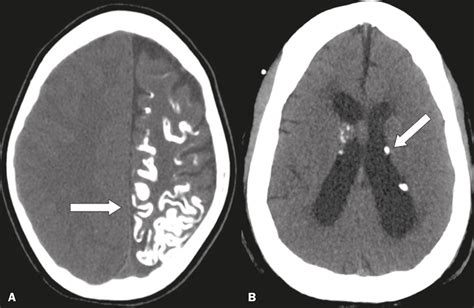

• Intracranial Calcifications: Found within the brain, these require closer monitoring as they can sometimes, though not always, be linked to congenital infections or certain genetic conditions.

Intracranial Requires thorough investigation to rule out congenital infections.